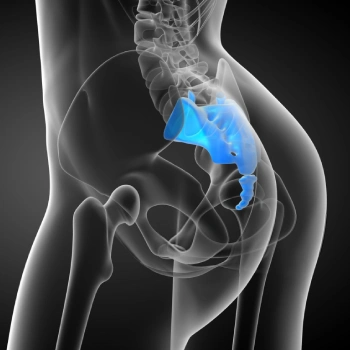

در این روش تصویر برداری یک صفحه (گیرنده یا دتکتور) در زیر عضو و قسمت مورد نظر قرار داده می شود و اشعه ایکس(دُز از اشعه جهت تشخیص) به همان قسمت که روی صفحه قرار گرفته تابنده می شود و توسط صفحه اطلاعات دریافت می شوند و همین اطلاعات پس از پردازش های لازم در نهایت عکس رادیولوژی به ما ارائه می دهد. کاربردهای رادیولوژی در منزل دقیقاً همان کاربرد رادیولوژی در بیمارستان ها می باشد از جمله بررسی انواع شکستگی ها، دررفتگی مفاصل، آرتروز مفاصل، دیدن پروتز های داخل استخوان از نظر بررسی موقعیت پروتز، آب آوردگی ریه(اِدم وافیوژن) و عفونت ریه، شکستگی دنده ها، انساد و وجود هوا در شکم و… می باشند. رادیولوژی در منزل تمام این خدمات را ارائه می دهد.

تصاویری از رادیولوژی در منزل توسط گاما پرتو